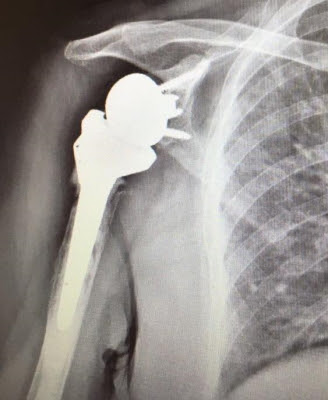

Las indicaciones relativas de la artroplastia anatómica total de hombro (TSA) y la artroplastia reversa de hombro (RSA) continúan evolucionando. Algunos cirujanos prefieren RSA sobre TSA para pacientes ancianos con osteoartritis glenohumeral primaria (GHOA) y un manguito rotador intacto debido al temor de un desgarro posoperatorio (secundario) del manguito rotador en este grupo de edad. Sin embargo, RSA se asocia con complicaciones únicas y un peor arco de movimiento funcional en comparación con TSA. Por lo tanto, es importante comprender los resultados clínicos y las tasas de cirugía de revisión y desgarros secundarios del manguito rotador en pacientes de edad avanzada sometidos a TSA.

Los pacientes de edad avanzada con GHOA primario y manguito rotador intacto tienen excelentes resultados clínicos y radiográficos después de la CST anatómica, con altas tasas de supervivencia del implante y una baja incidencia de desgarros secundarios del manguito rotador en los primeros cinco años postoperatorios. La edad mayor de setenta años por sí sola no debe considerarse una indicación de RSA sobre TSA.